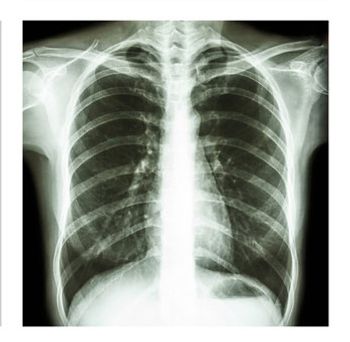

Case History: 49-year-old patient presented with history of cough; mild weight loss was noted.

Case History: 22-year-old patient presents with cough and breathlessness.